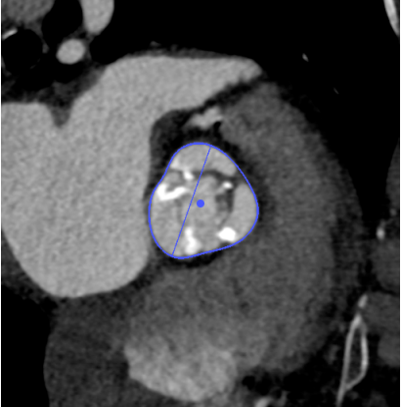

Annulus

长径: 24.8 mm

周长: 68.6 mm

面积: 352.3 mm²

SOV

27.3 x 25.8 x 25.9 mm

STJ

长径: 27.6 mm

周长: 84.4 mm

面积: 566.2 mm²

高度: 13.8mm

LCA

下缘高度 7.1mm

上缘高度 11.9mm

瓣叶长度 11.8mm

术后1w——冠脉CTA